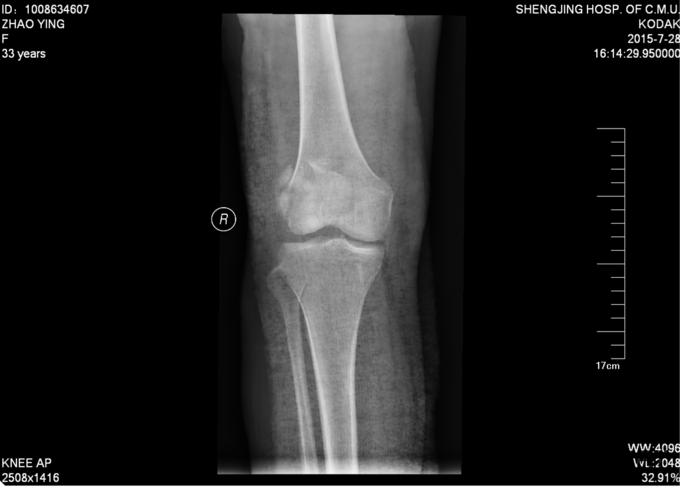

现病史:患者家属代诉于2015年7月23日5点发生车祸,车祸后致右膝部疼痛肿胀活动受限,当时无意识不清,120送至当地医院(辽中县医院),后为进一步治疗,急诊就诊于中国医科大学附属盛京医院,行X线片检查示:右髌骨开放性骨折,急诊给予清创缝合,观察患者病情稳定后,急诊以“右髌骨开放性骨折”为诊断收住我科·。伤来患者无头痛及发热,无咳嗽咳痰,无腹痛及恶心呕吐,饮食睡眠可,大小便正常。

专科查体:患者轮椅入病房,右膝部不规则缝合术后,右膝部肿胀明显,疼痛,压痛(+),活动受限,骨擦音,骨擦感(+), 患肢足趾活动可,足背动脉可触及。

入院后完善检查,患者创口换药,观察患者创口变化,于一周后无红肿渗出后,无发烧发热后。查无手术禁忌症后行右髌骨骨折切开复位张力带内固定术